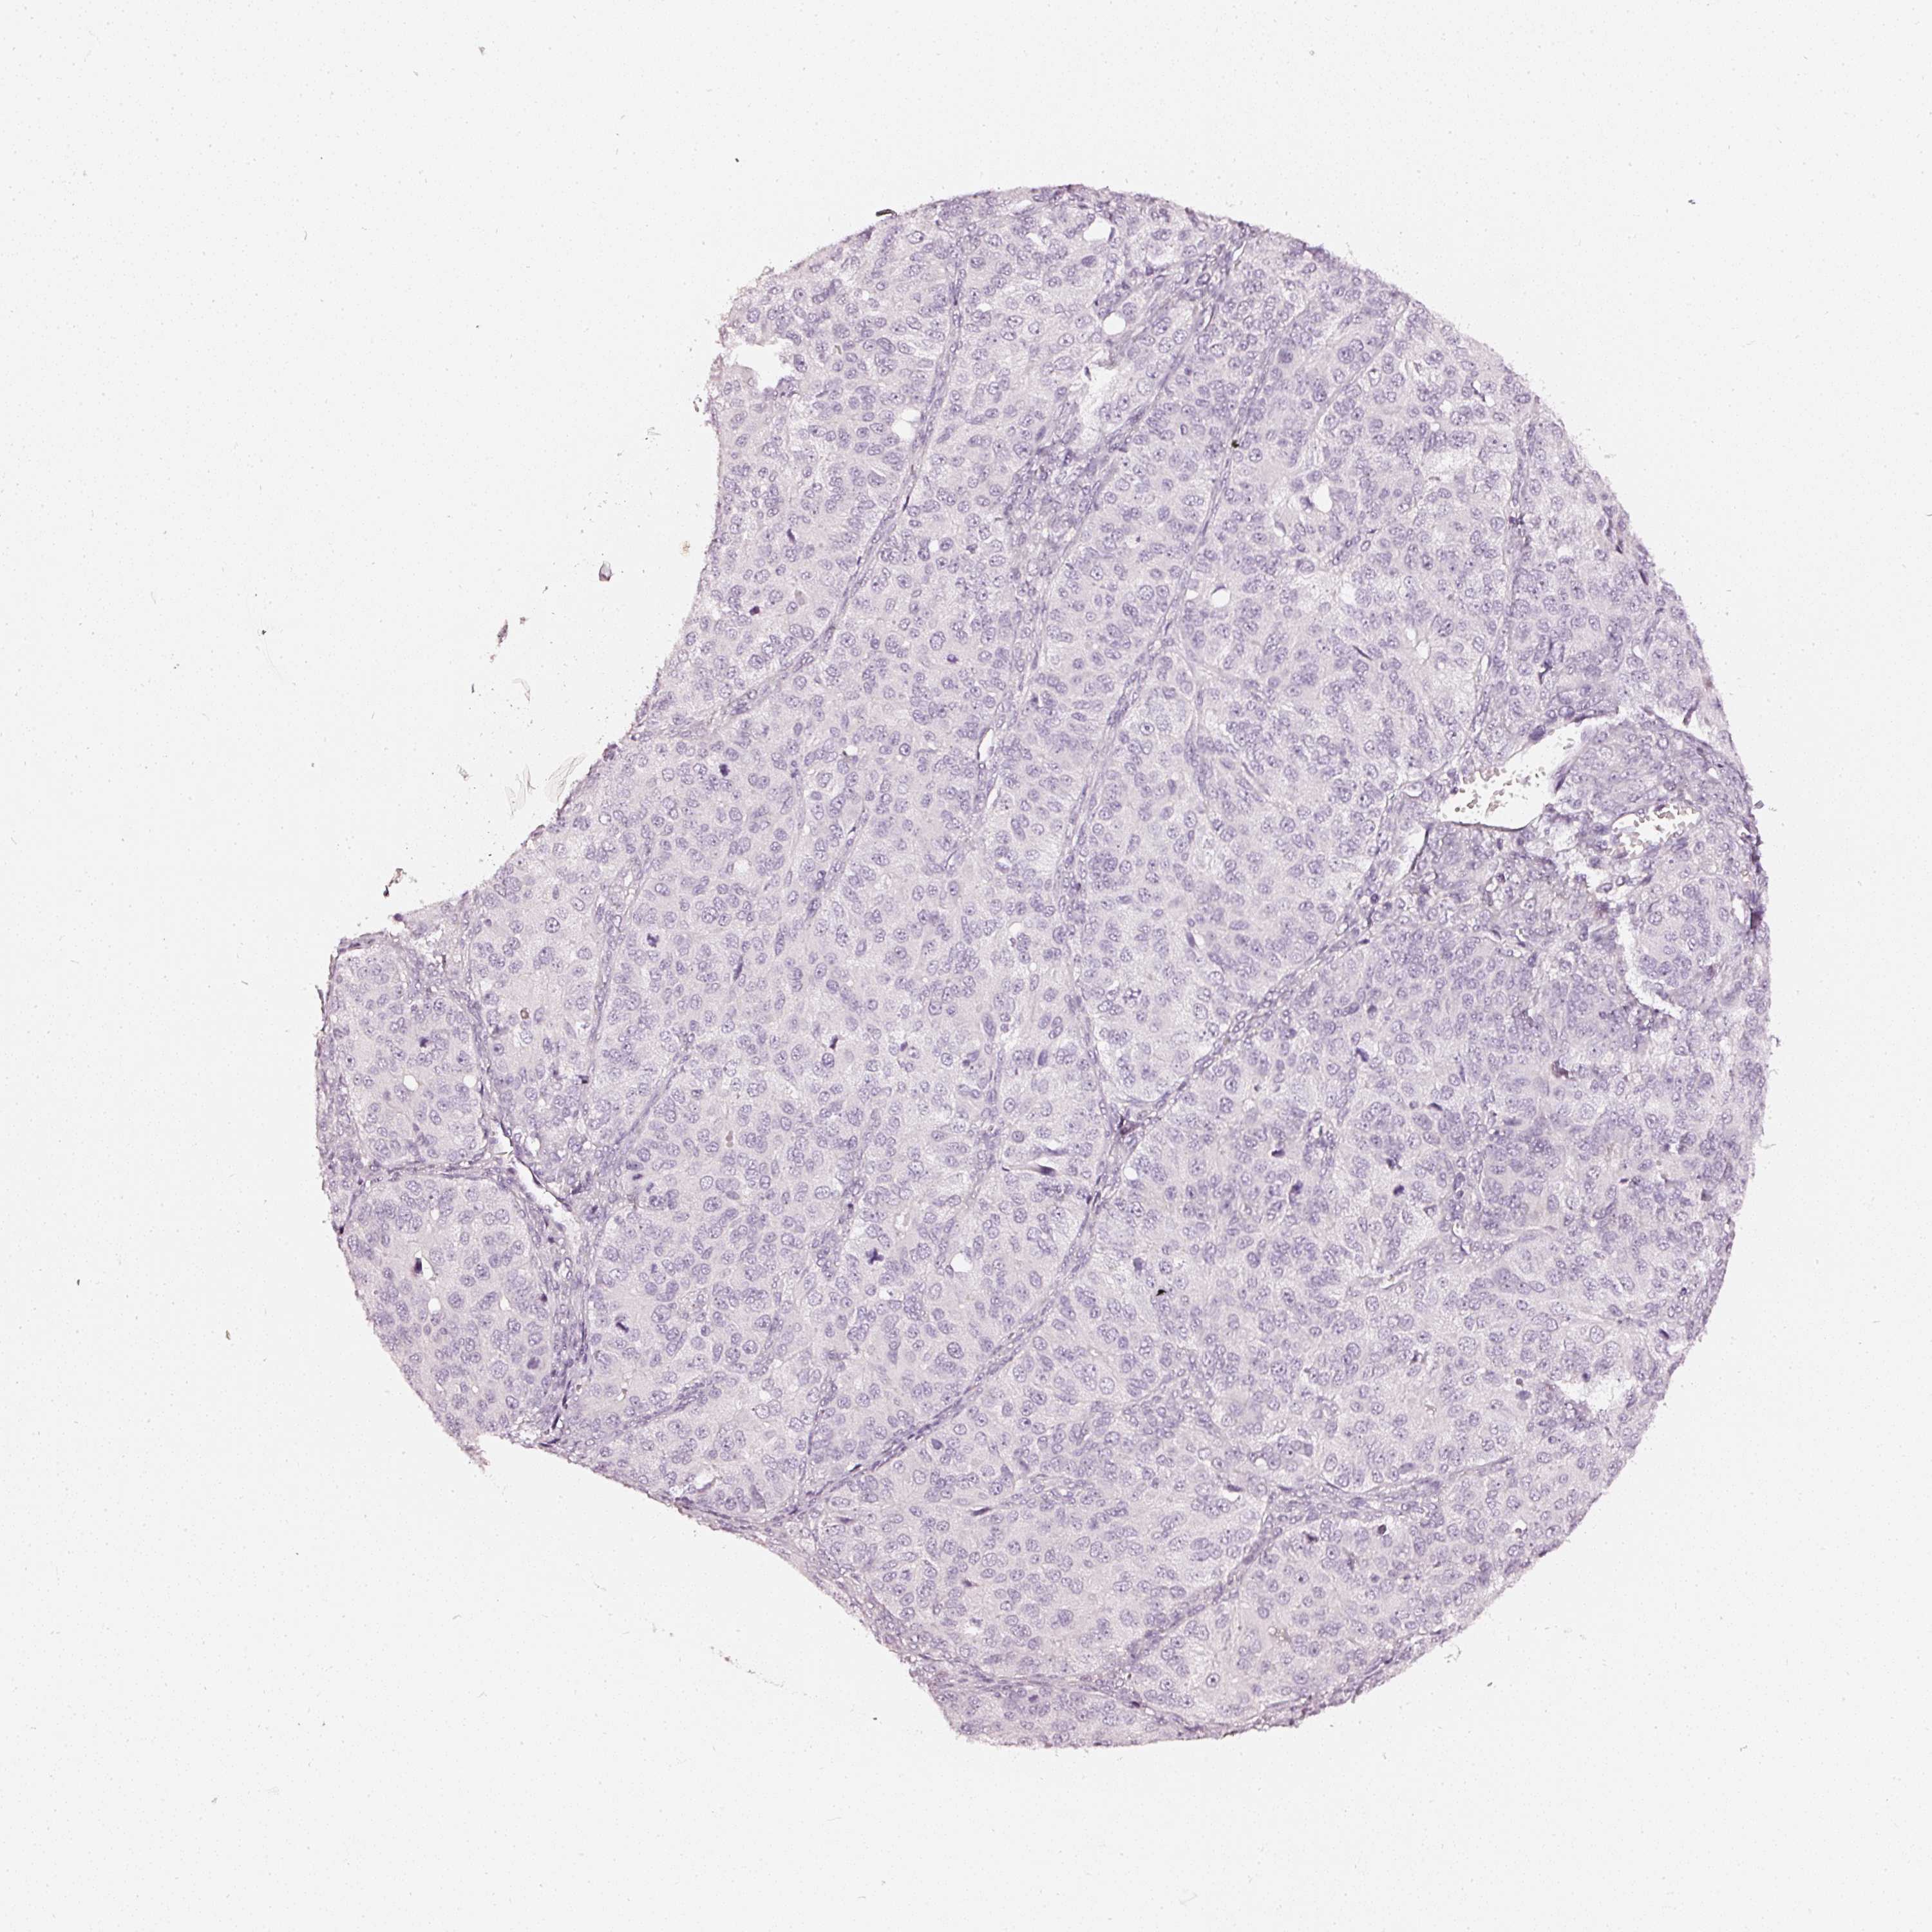

OVARIAN CANCER - Protein expressioni

A mouse-over function shows sample information and annotation data. Click on an image to view it in a full screen mode. Samples can be filtered based on level of antibody staining by selecting one or several of the following categories: high, medium, low and not detected. The assay and annotation is described here.

Note that samples used for immunohistochemistry by the Human Protein Atlas do not correspond to samples in the TCGA dataset.

Antibody stainingi

Antibody staining in the annotated cell types in the current human tissue is reported as not detected, low, medium, or high, based on conventional immunohistochemistry profiling in selected tissues. This score is based on the combination of the staining intensity and fraction of stained cells.

Each image is clickable and will lead to virtual microscopy that enables deeper exploration of all samples and also displays staining intensity scores, fraction scores and subcellular localization as well as patient and tissue information for each sample.

HPA023280

Cystadenocarcinoma, mucinous, NOS